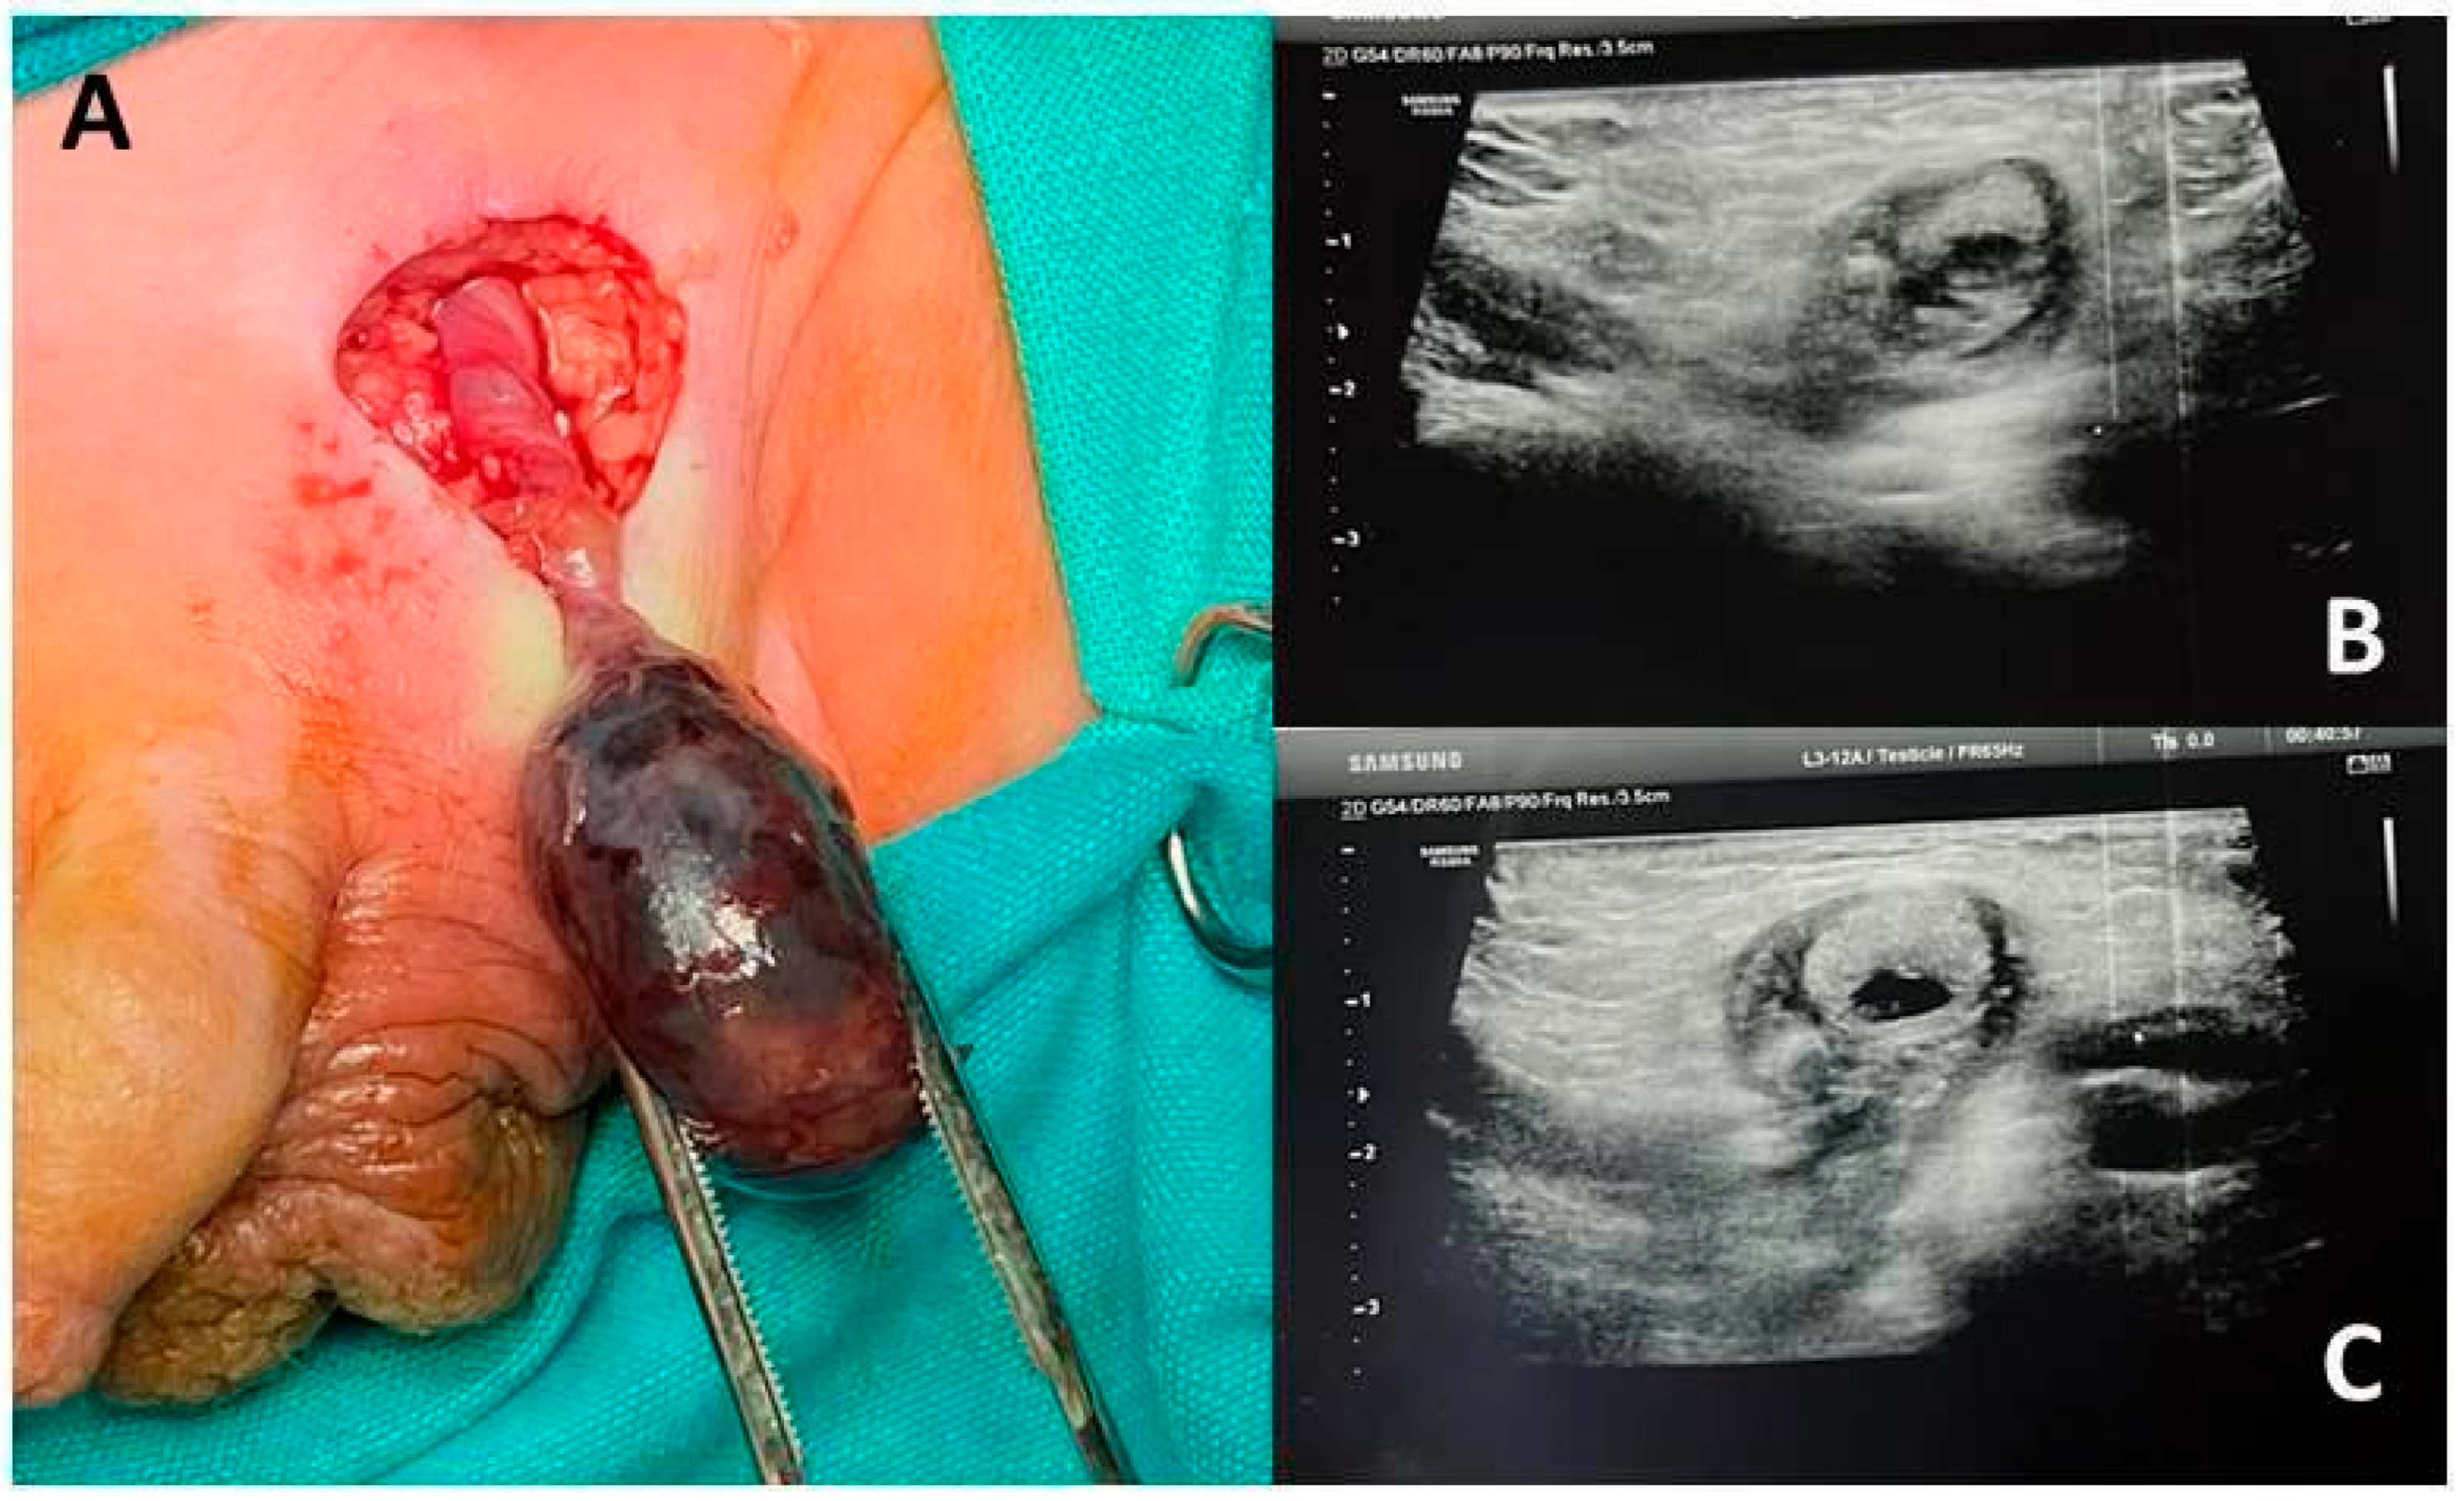

| 7 | L | 36 h | Inconsolable crying, inguinal swelling, and pain | Orchiectomy |